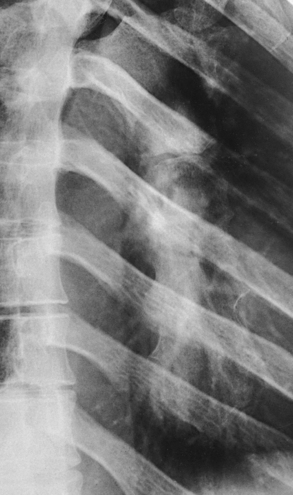

In radiography of the ribs, the patient is usually examined with respiration suspended in either full inspiration or expiration. Occasionally, shallow breathing may be used to obliterate lung markings. If this technique is used, breathing must be shallow enough to ensure that the ribs are not elevated or depressed as described in the anatomy portion of this chapter. Examples of shallow breathing and suspended respiration are compared in Figs. 9-35 and 9-36.

Rib fractures can cause a great deal of pain and hemorrhage because of the closely related neurovascular structures. This situation commonly makes it difficult for the patient to breathe deeply for the required radiograph. Deeper inspiration is attained if the patient fully understands the importance of expanding the lungs and if the exposure is made after the patient takes the second deep breath.